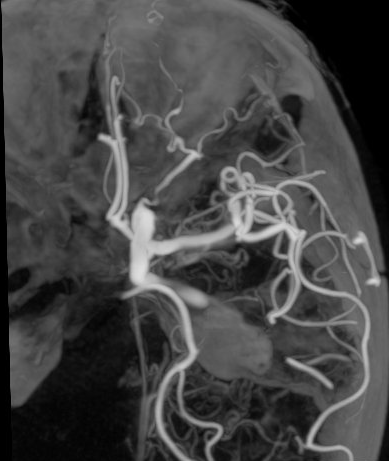

Angiografia cerebrale di controllo post-operatorio

Clipping di aneurisma complesso M1-M2 di sinistra – ricostruzione biforcazione arteria cerebrale media